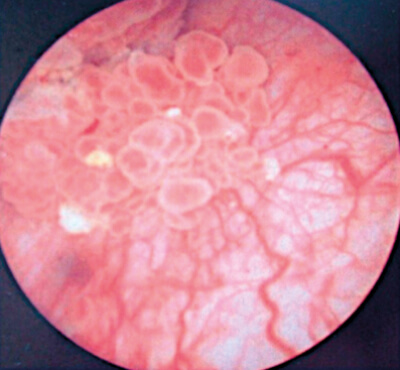

- What does this image show?

1. A <3cm bladder tumour with a papillary appearance.